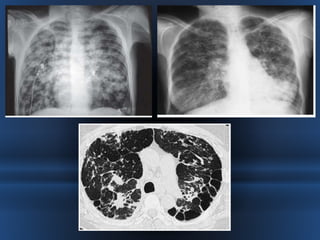

RADIOGRAFIA.

• La sensibilidad de la radiografía de tórax varia de un 45 a un 70% en relación

al diagnóstico de las bronquiectasias.

• Las bronquiectasias producen engrosamiento de la pared bronquial originando

el signo “ en raíles de tren” (tram lines).

• Acúmulo de secreciones a nivel bronquial ,“signos del dedo de guante”

• Imágenes quísticas, a veces incluso con nivel hidroaéreo y opacidades

anulares.

• El apelotonamiento de bronquiectasias quísticas en una zona pueden dar una

imagen similar a la del pulmón en panal.

• Atelectasias por obstrucción por tapones mucosos

TOMOGRAFIA COMPUTARIZADA DE ALTA RESOLUCION

= GOLD STANDARD

RADIOGRAFIA. • Lasensibilidad de la radiografía de tórax varia de un 45 a un 70% en relación al diagnóstico de las bronquiectasias. • Las bronquiectasias producen engrosamiento de la pared bronquial originando el signo “ en raíles de tren” (tram lines). • Acúmulo de secreciones a nivel bronquial ,“signos del dedo de guante” • Imágenes quísticas, a veces incluso con nivel hidroaéreo y opacidades anulares. • El apelotonamiento de bronquiectasias quísticas en una zona pueden dar una imagen similar a la del pulmón en panal. • Atelectasias por obstrucción por tapones mucosos

TOMOGRAFIA COMPUTARIZADA DEALTA RESOLUCION = GOLD STANDARD